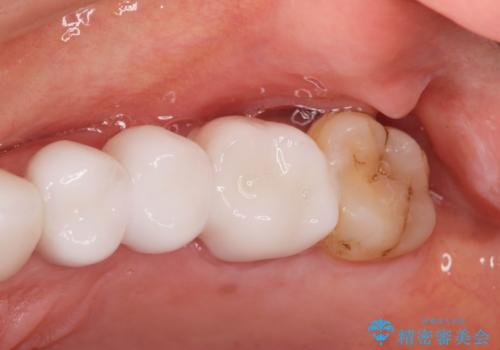

- 39.6万円(ジルコニアクラウン×3・仮歯×3)費用は治療当時の料金となります

治療前よりも高い位置で歯ぐきが保たれ、清掃性の高いブリッジ治療を行うことができました。